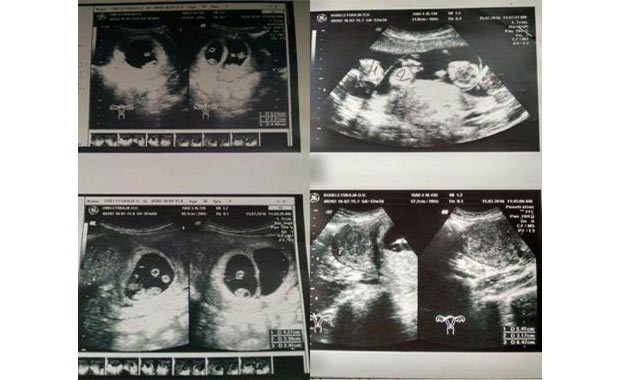

Hamileliğinin erken döneminde Oksana birden fazla bebeği karnında taşıyormuş hissine kapıldı. The Mirror’a konuşan Oksana, “Ailemizde kimse buna benzer bir şey tecrübe etmemişti. İtiraf etmeliyim ki gelişmeler sonrasında ben de şok geçirdim” dedi.

Genç kadın, “Doktor müjdeyi verince kalbim durmak üzereydi. Bana ‘Muhtemelen bir villada yaşamanız gerekecek. Karnında beş veya altı bebek görüyorum’ diye konuştu...

Doğumuna 8 doktor giren Oksana, sezaryen ile üç erkek ve iki kız çocuk dünyaya getirdi.